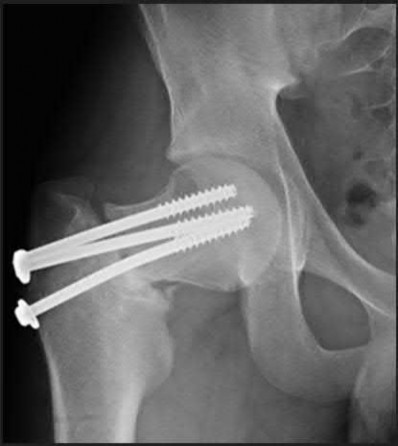

A 46-year-old competitive cyclist falls while racing and suffers an isolated fracture as seen in Figure A. He is positioned on a fracture table and a closed reduction maneuver is attempted, unsuccessfully.

Which of the following treatment plans is most appropriate?

When standard closed reduction maneuvers using a traction table are unsuccessful, displaced femoral neck fracture in young adults (10 degrees varus/valgus or anteversion/retroversion) or has

significant displacement (5 mm or more in ANY view) is unacceptable, and an open reduction should be performed. Of course, this can be very difficult to assess in the operating room, where uncalibrated fluoroscopy with difficult to obtain tangential imaging is heavily relied upon to make this assessment.

Accordingly, when the quality of closed reduction is questionable, the best treatment plan is to obtain a better reduction with direct visualization of the femoral neck prior to fixation.

A systematic review of the literature by Pauyo, et al. cites numerous studies showing a higher incidence of osteonecrosis of the femoral head in patients with displaced femoral neck fractures treated with unsatisfactory reductions. Furthermore, performing multiple closed reduction attempts is also associated with a higher risk of osteonecrosis.

Upadhyay et al. performed a randomized controlled trial of 102 patients with femoral neck fractures treated with closed or open reductions, which were randomized. The groups had similar rates of nonunions and osteonecrosis of the femoral head; however, subanalysis revealed a "poor" reduction was the highest predictor of poor outcome, whether the reduction was attempted open or closed. Interestingly, the quality of reduction was more important than the implant used or the timing of surgery (including surgeries performed > 48h after injury).

Figure A shows a pre-operative AP x-ray of the patient's high-energy femoral neck fracture. Illustrations A and B are intraoperative fluoroscopic and postoperative CT scans of this same patient, highlighting that fluoroscopy may "hide" the degree of residual displacement.